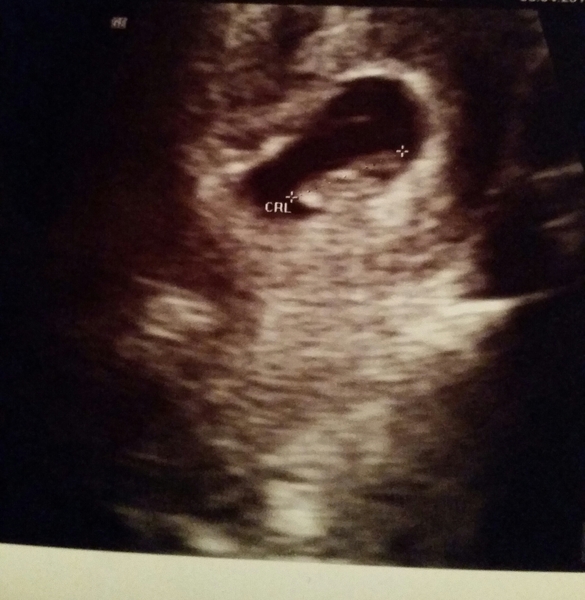

Scan went well. Measuring spot on at 8+1.

Scan was an external scan (though last one was tv and was absolutely fine) and heartbeat was lovely and clear.